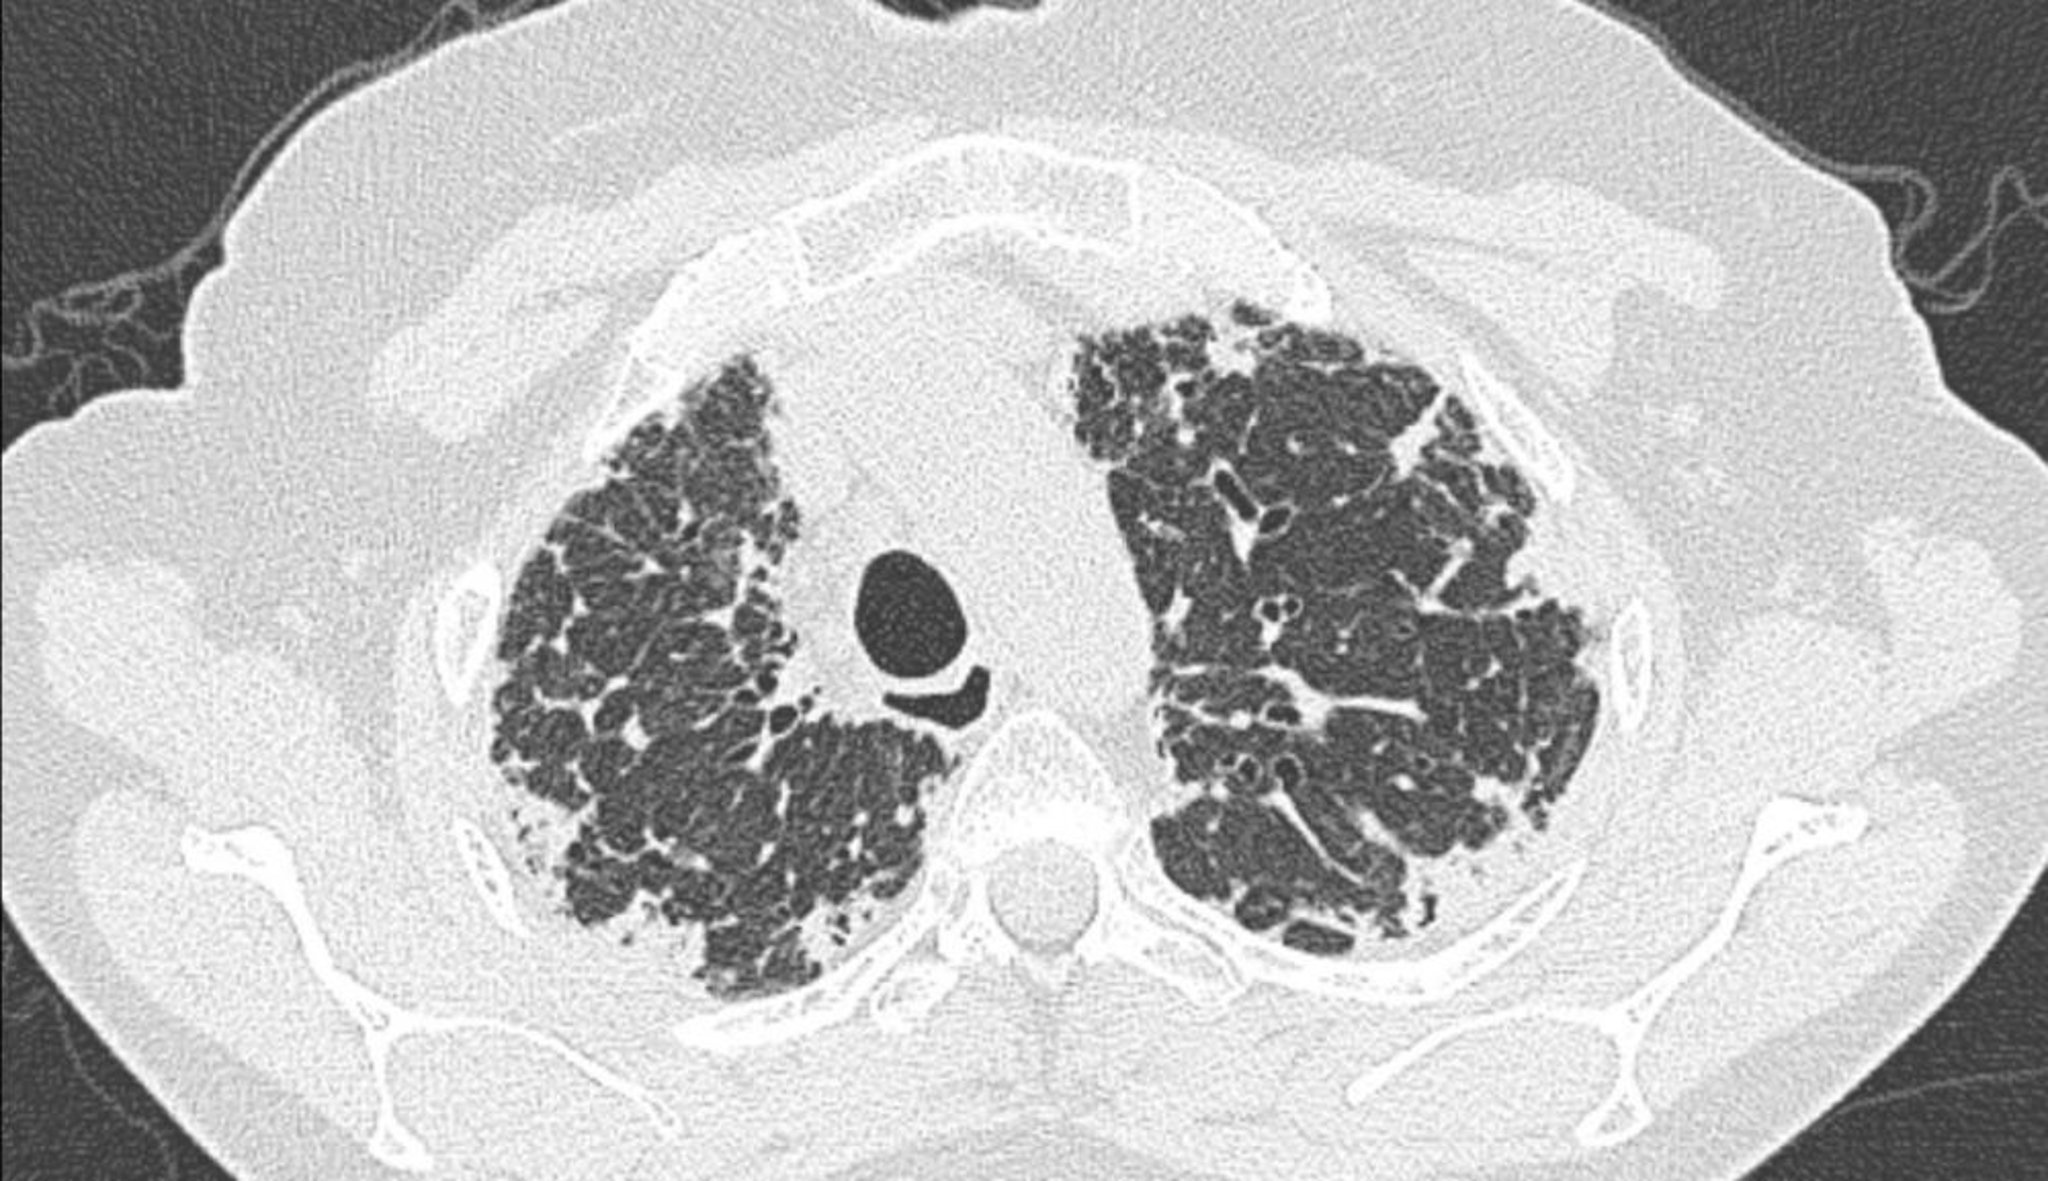

Fibroelastosis pleuroparenquimatosa idiopática (TC)

La tomografía computarizada de tórax muestra engrosamiento pleural y subpleural.

Image courtesy of Joyce S. Lee, MD, MAS.